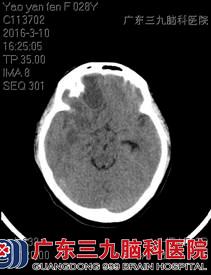

术前CT

姚某,女性,28岁,三个多月前,姚女士无明显诱因出现头痛的问题,头痛呈持续性的胀痛,她在当地医院检查头部CT,报告显示“未见明显异常”,医生给予药物治疗(具体不详)后,其症状无明显缓解。半个多月后,姚女士感觉头痛的症状比之前加重了,还伴随恶心呕吐,家人急忙将她转入广东三九脑科医院治疗。

入院后,神经外六科的医生为她急查头部MR,结果提示:考虑右侧额叶及右侧基底节区多发脑脓肿,合并邻近右侧额部硬膜外少量积脓。结合姚女士的症状及病史,医生判断有手术指征。完善了所有的术前准备后,医生为其全麻手术,用神经导航及B超结合定位,切除右额、基底节区多发脑脓肿,手术过程很顺利。